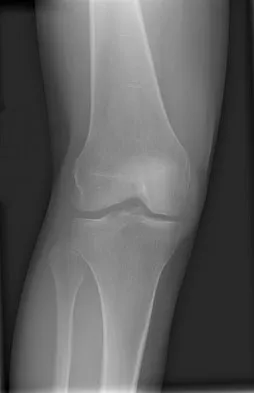

A 58-year-old man has anterior knee pain after undergoing total knee arthroplasty for osteoarthritis 2 years ago. He denies any history of trauma. A Merchant view is shown in Figure 20. What is the most likely cause of his pain?

Explanation

The patient has a patellar stress fracture after resurfacing in a total knee arthroplasty. Several studies have shown that over-resection of the patella to less than 12 to 15 mm increases anterior patellar surface strains to a point where the risk of fracture is increased. Increasing the patellar thickness, positioning of the femoral component, lateral releases, and component types have not been clearly associated with increased fracture risk. Reuben JD, McDonald CL, Woodard PL, Hennington LJ: Effect of patella thickness on patella strain following total knee arthroplasty. J Arthroplasty 1991;6:251-258. Hsu HC, Luo ZP, Rand JA, An KN: Influence of patellar thickness on patellar tracking and patellofemoral contact characteristics after total knee arthroplasty. J Arthroplasty 1996;11:69-80.